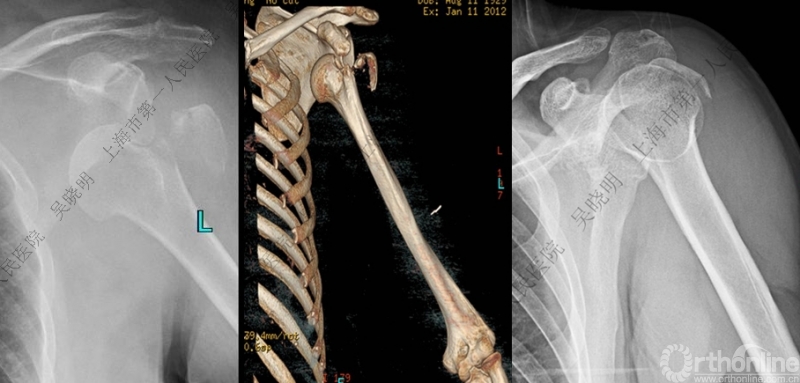

下图考虑为孤立性的大结节骨折?

看完片子,你会发现高质量的平片甚至3D CT也难以发现

X线看不清骨折线,三维CT也看不清